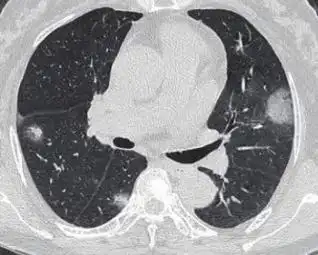

新冠病毒感染所引发的病症就是新冠肺炎,使得这种状况出现的那类病原体是新型冠状病毒,此病毒主要是凭借呼吸道飞沫以及密切接触来进行传播,在处于密闭空间的时候还存在着通过气溶胶传播的可能性,而人群对于新冠病毒广泛地呈现出容易被感染的情况。

遭受感染之后,常见的症状涵盖发热,还有干咳以及乏力。有一部分患者会展现出嗅觉或者味觉减退,甚至是丧失的情况,而这种状况在其他呼吸道感染之中是比较少见的。需要引起注意的是,存在一些感染者有可能完全不存在症状,然而同样具备传染性,这样的情况增加了防控的难度。